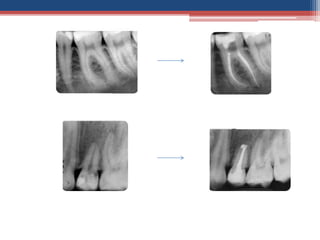

Glide path was created in the DB canal

Glide path wascreated in the DB canal